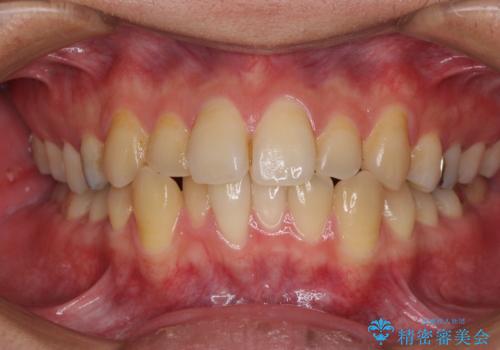

前歯のクロスバイトをインビザラインで矯正治療

- 前歯のデコボコとクロスバイトを気にして来院された患者様です。

前歯を早く整えたいとの希望があったので、ワイヤー矯正にて短期間でクロスバイトを解消し、その後インビザラインにて整えることとしました。